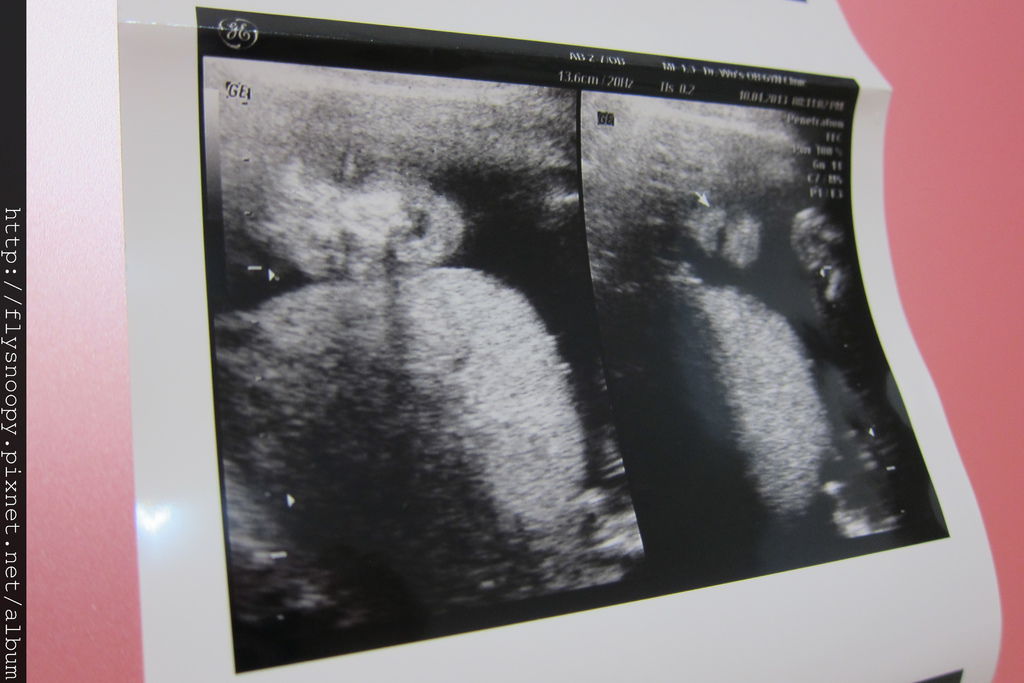

第二張左邊是baby的腳